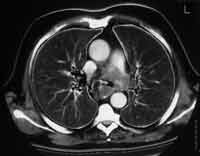

Рис. 3. Центральный рак легкого у больного К. , 53 года. КТА легочных артерий. Дефект контрастирования ствола и левой легочной артерии вследствие инвазии опухолью.